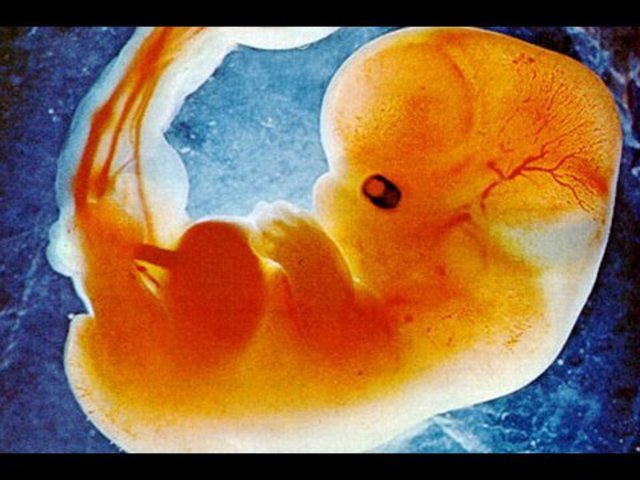

• Month 2

Month 2

About 1/4 an inch long at the beginning of this month

face eyes ears and limbs take shape

bones begin to form